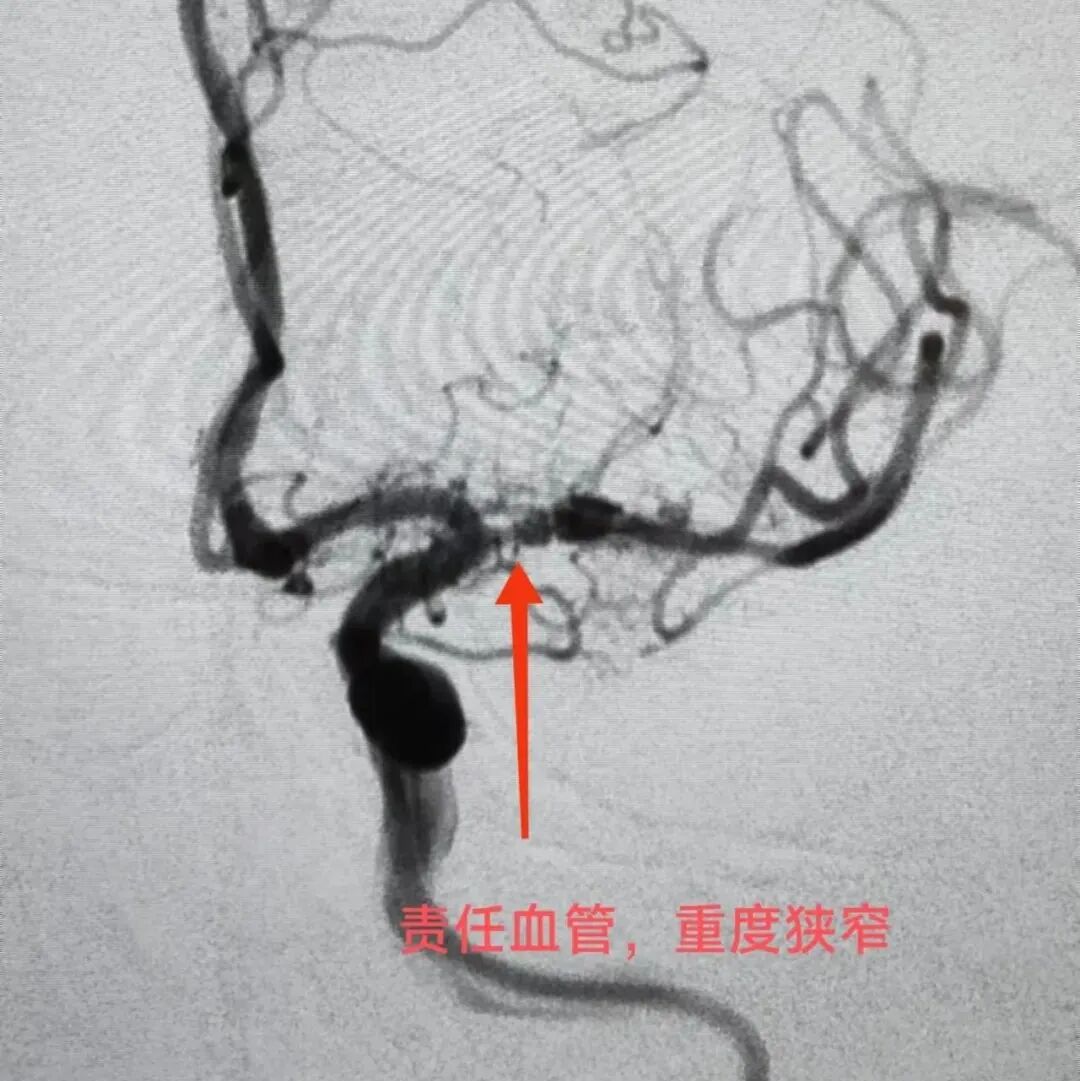

??责任血管,重度狭窄